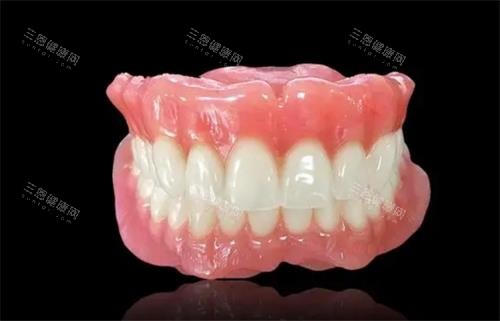

活动性义齿和吸附性义齿,看着都是“能拿下来的假牙”,但固位原理天差地别!一个靠卡环硬拽,一个靠“吸力”贴合,用错类型等于白花钱还遭罪!今天咱们就掰开了揉碎了讲,到底该怎么选?

吸附性义齿,则是近十年流行的“黑科技假牙”。它不依赖卡环,而是通过特殊设计的基托边缘,像吸盘一样紧密贴合牙槽嵴(牙床凹陷处),利用大气压力和唾液吸附力“吸”在嘴里。就像把吸盘挂钩按在光滑瓷砖上,按压越紧,吸附越牢。

吸附性义齿的基托边缘经过精密计算,会延伸到黏膜皱襞(牙床上的小凸起)区域,戴的时候需要医生用专科手法按压排空空气。当基托与牙槽嵴完全贴合后,外部大气压力会把假牙牢牢“压”在嘴里,就像吸盘吸住玻璃一样。

更出色的是,它还能根据患者牙槽骨的形态个性化调整。比如上颌牙槽骨高的,基托边缘会设计得更宽;下颌牙槽骨凹陷的,会加强边缘封闭性。网友@王阿姨分享:“我全口牙掉了三年,戴普通假牙总流口水,换吸附性的当天就能啃苹果,邻居都问我是不是偷偷去种牙了!”